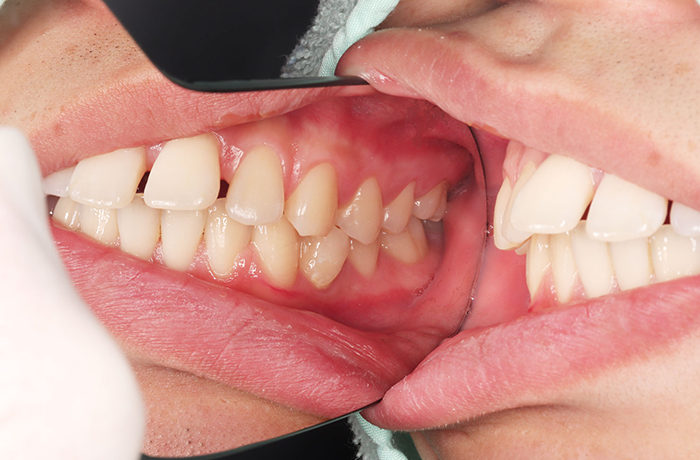

治療前

before

患者の症状 叢生、正中のずれ、上顎左右側切歯の口蓋側転位(交叉咬合)

治療方法 非抜歯で、マウスピース型カスタムメイド矯正歯科装置(インビザライン)による矯正

歯列弓を拡大することで非抜歯を可能にしました。

治療結果 側切歯の交叉咬合は解消、上下正中のずれも改善し咬み合わせが良くなりました。